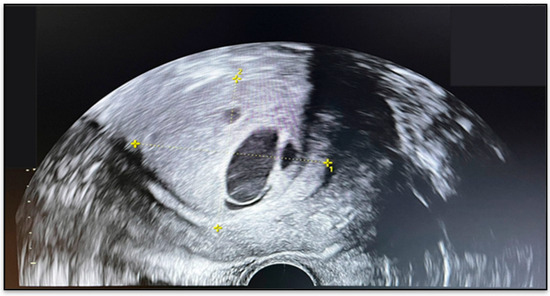

2.2. Imaging Findings